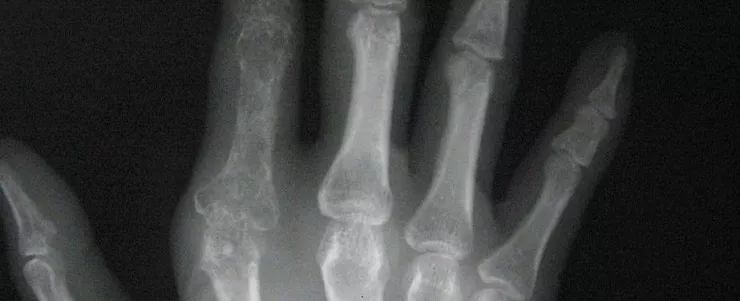

一、450名骨科医生不敌AI阅片

5月11日上午在中国医师协会骨科医师分会年会上, 450名骨科医生对战骨科AI智能阅片,AI得90分,略高于医生综合得分。